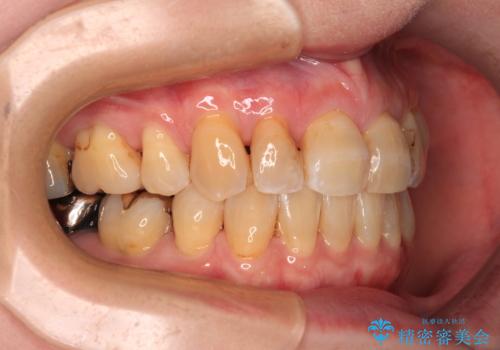

- 口元の突出感を気にして来院された患者様です。

上下前歯が著しく前突している状態であったので、上下左右の小臼歯4本を抜歯し、ワイヤー装置にて矯正治療を行うこととしました。

上顎左側は第二小臼歯に大きなむし歯があったため、通常は第一小臼歯を抜歯するところ、イレギュラーに第二小臼歯を抜歯することとしました。

抜歯する第二小臼歯の後方の歯は神経近くにまで及ぶむし歯があったため、事前に処置をしておき、矯正治療後にオールセラミッククラウンにて補綴治療を行うこととしました。